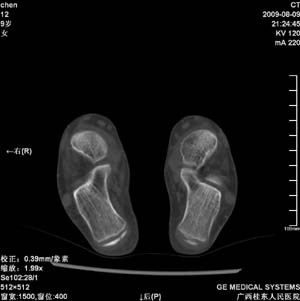

标题: PED2867:右侧内踝肿胀,骨质改变,请各位老师会诊 [打印本页]

标题: PED2867:右侧内踝肿胀,骨质改变,请各位老师会诊

九岁小朋友,近期左侧内踝疼痛,局部肿胀,平时无特殊,近期经常溜干冰

对不起,是右侧内踝肿胀

双踝关节骨质及发育未见异常。

左侧内踝密度增高,请结合临床!